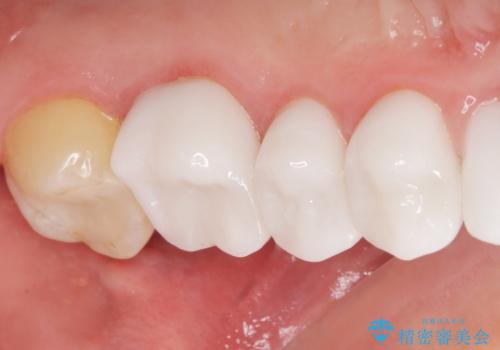

歯頚ラインが変えられないことや天然歯を削るリスクをご理解頂いた上で、オールセラミッククラウンによる補綴治療を行いました。(見えない奥歯のみ天然歯のままとしました)

それ以外の歯は神経をとらずに済むよう、慎重かつ丁寧に歯の形態を整えました。

クラウンの色味に関して、自然な白さ(シェードA1~NW0.5)のクラウンを作製・試適したところ「もっと白くしたい」と希望され、当院で最も明度の高い色(シェードNW0)に修正しました。

被せ物の種類:オールセラミッククラウン スタンダード (シェード:NW0)